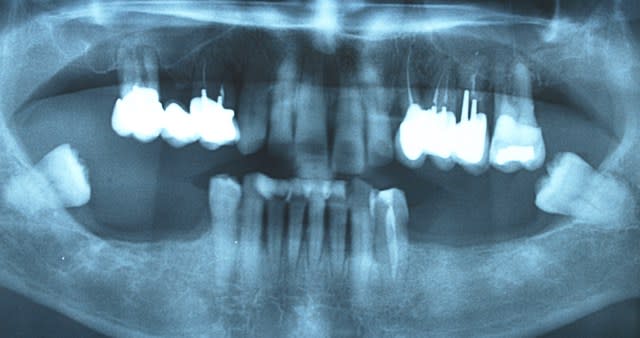

REPONSE: ci joint photos du depart.ttt un bridge de contention avec paro

t'rappelles a l école quand..........Bon voila la radio panagerique.Je t'ai pris une bonne mutuelle tu vas te gaver.